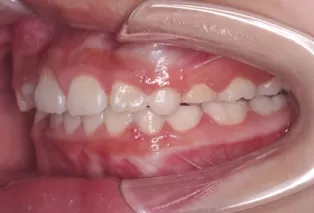

Photos intra-orales